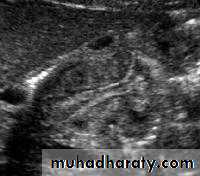

Hypertrophic pyloric stenosis refers to idiopathic thickening of gastric pyloric musculature which then results in progressive gastric outlet obstruction

In a normal situation, the pyloric muscle thickness (diame­ter of a single muscular wall on a transverse image) should normally be less than 3 mm (most accurate 3) and the length (longitudinal measurement) should not exceed 15 mm.